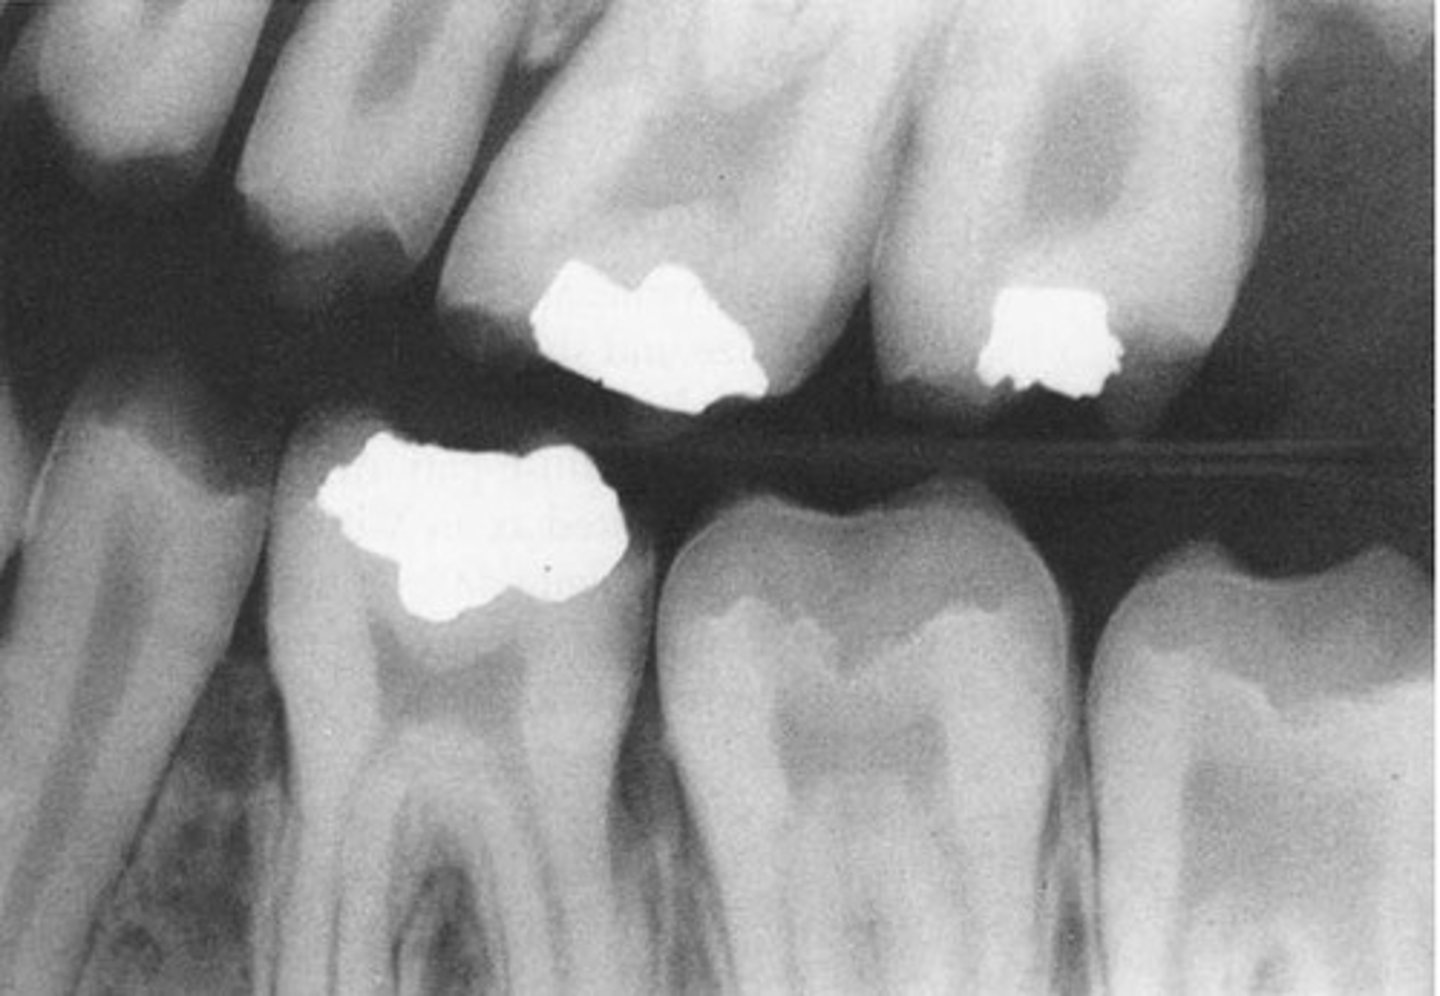

-more radiopaque than dentin

-radiodensity like dentin

-on XR → no pulp/short roots/periapical radiolucencies